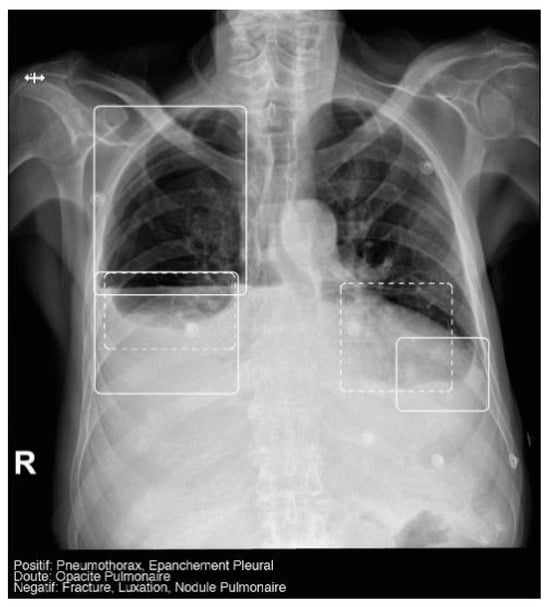

The AI software (Arterys Chest MICA v29.4.0, developed by Arterys, a company based in Paris, France) was the World’s First Online Medical Imaging Platform 100% Cloud native, powered by AI and FDA cleared. It was a clinical application (CE marked as a Class IIa medical device) designed to process thoracic radiographic series and identify five imaging findings (categorical variables): pulmonary nodule, pulmonary opacity, pleural effusion, pneumothorax, and fracture. Each detected finding was localized in the image using a bounding box and was assigned a confidence label, either “positive” (continuous line) or “doubtful” (dashed line). Moreover, the algorithm provided a list of findings not detected in the current radiographic view (Figure 2). All findings were detected by a deep learning model that processed all radiographic views included in the series.

The AI results were integrated into the institutional picture archiving and communication system (PACS) and the clinicians’ image viewer, being displayed in a secondary capture apart from the original radiograph. In practice, radiologists first evaluated the chest X-ray images and then reviewed the AI results on the reading workstation to assist in completing the radiology report. When the requesting physicians opened the chest X-ray in the viewer, they could also see the AI’s analysis.

Figure 2. Chest radiograph with AI analysis, which detected a positive right pneumothorax, positive bilateral pleural effusion (both outlined with continuous boxes), and doubtful bibasilar opacities (outlined with discontinuous boxes).